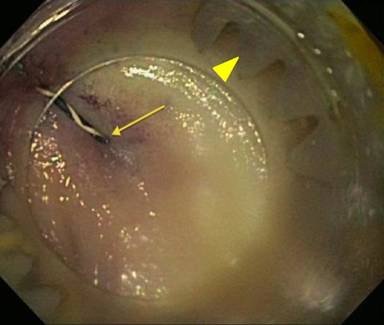

Because pancreatic sphincterotomy and pancreatic duct stenting was unsuccessful, we attempted endoscopic clip closure of the fistula. A 0.025” angled guidewire was advanced into the pancreatic duct, across the fistula, and into the colon. The duodenoscope was removed, leaving the wire in place. An over-the-scope clip (Ovesco, Campbell, CA, USA) was attached to the end of a colonoscope which was advanced to the splenic flexure (Figure 2). The fistula was identified by the wire protruding from it (Figure 3). The cap was positioned en face to the fistula and the wire slowly withdrawn. Using a grasper, tissue was pulled into the cap and suction applied. The clip was deployed and in good position (Figure 4).

Figure 3. An endoscopic view of the angled guidewire protruding through the fistula (arrow) and the over-the-scope clip (arrowhead). |